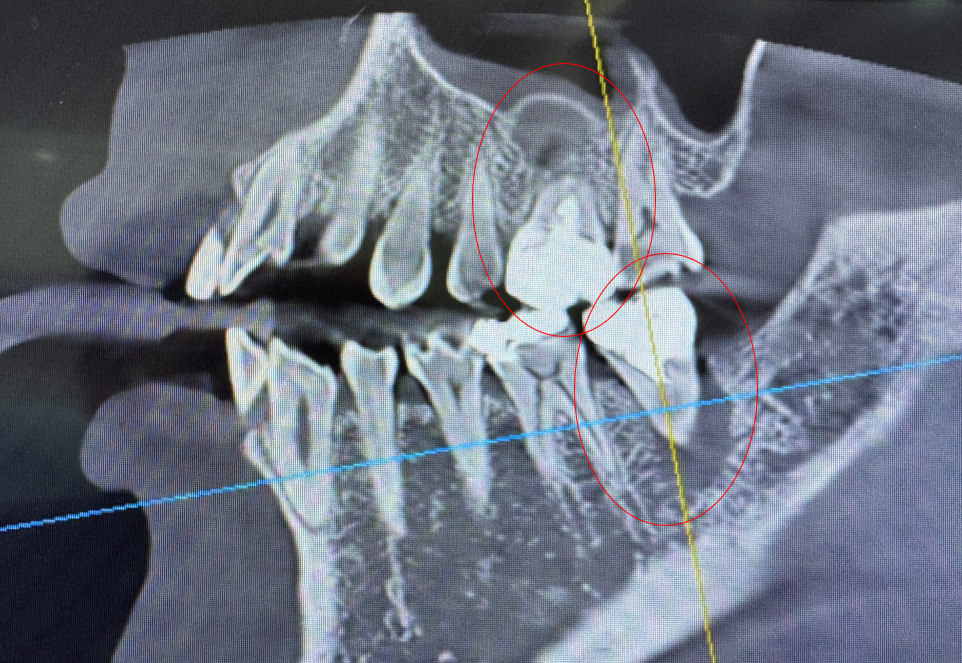

이빨이 너무 갑자기 아파져서 동네 의원가서 CT 찍어보니까 이빨 2개 염증이 너무 커서 뼈 다 녹였다고 한다.. 이거 발치 하고 염증 다 긁어내고 임플란트 박아야한다고 함..

근데 윗 이빨의 경우 염증이 위의 공기주머니(상악동) 와 너무 가까워서 잘못하면 천공(구멍이 뚫림)이 생길 수 있다고 하여 큰병원에 가라고 권유해서 바로 대학병원 예약..